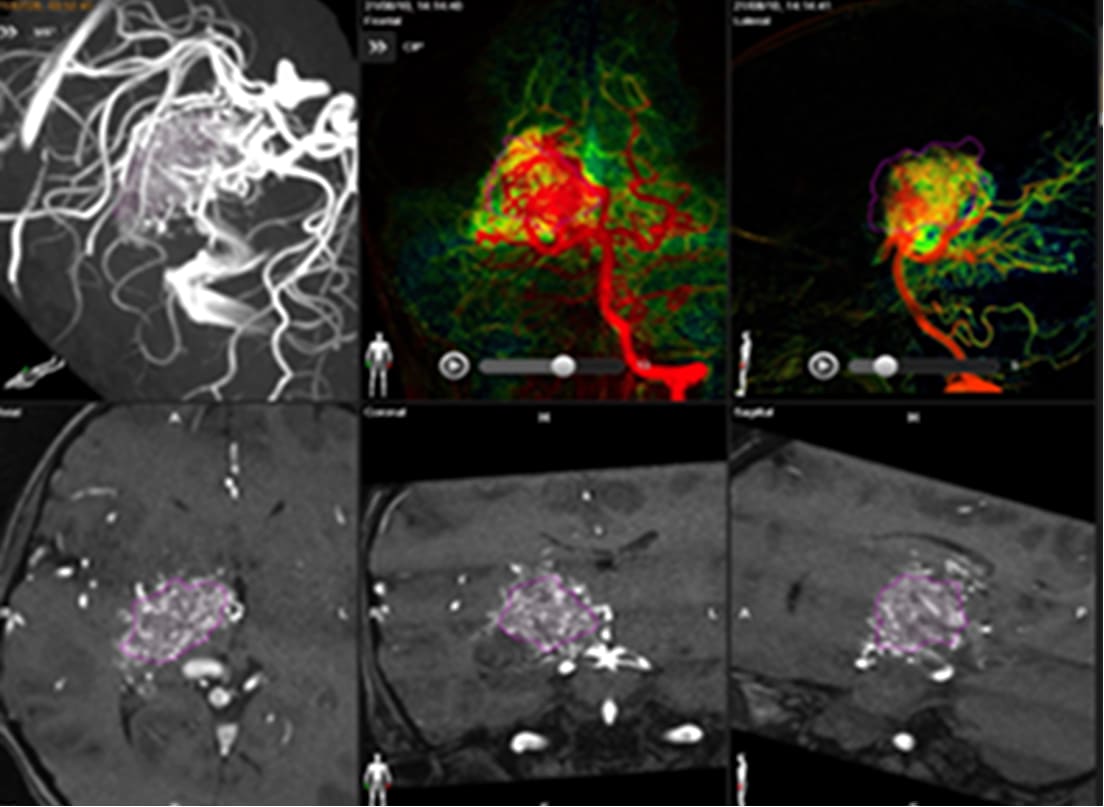

ブレインラボ・エレメンツ

における治療ターゲッテイング

データインストール後の

ガンマプランにおける治療計画